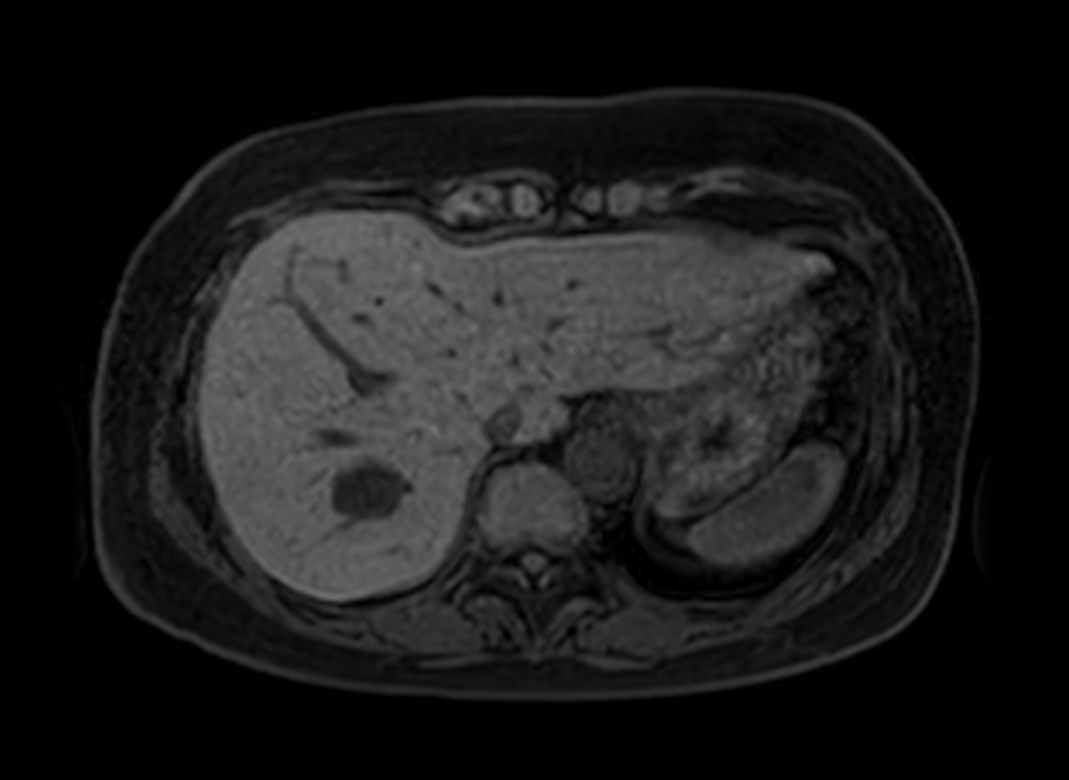

Axial mDIXON XD FFE (In Phase)